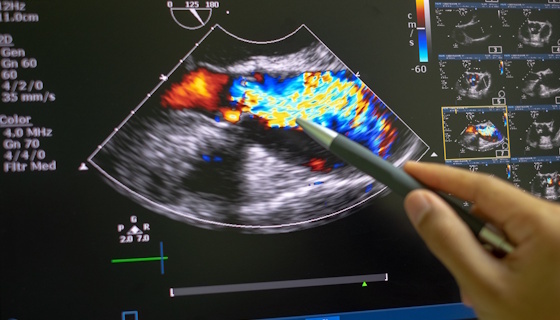

Quantification et prise en charge des valvulopathies gauches régurgitantes

Pathologies valvulaires : évaluation échographique et prise en charge